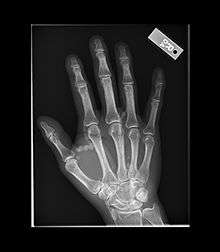

Tumoral calcinosis is a rare condition in which there is calcium deposition in the soft tissue in periarticular location i.e. around joints.[1] The accumulations are outside the joint capsule. They are frequently seen in patients undergoing renal dialysis. It is also considered by some to have a hereditary predisposition. The name indicates calcinosis (calcium deposition) which resembles tumor (like a new growth). They are not true neoplasms - they don't have dividing cells. They are just deposition of inorganic calcium with serum exudate. Children and adolescents (6 to 25 years) are the most commonly affected. The symptom that the accumulations cause is not pain but swelling around joints. They have propensity to enlarge progressively and ulcerate the overlying skin and extrude. They are most common around shoulders, hips and elbows. Laboratory evaluation reveal normal serum calcium levels and hyperphosphatemia. Rarely ALP (alkaline phosphatase - an enzyme active at sites of bone formation) may be elevated. Treatment is normalization of serum phosphate levels and resection of lesion. Surgical removal should be complete and if part of it is left, there is inevitable recurrence. Cutting through the excised calcium deposition reveals semifluid calcium suspension in albumin encapsulated by fibrous tissue.